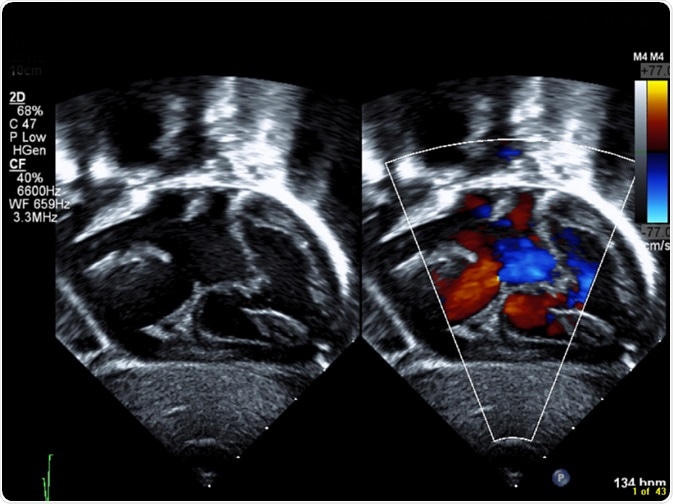

Septal Defect

Image Credit: Sumer McNitt/Shutterstock.com